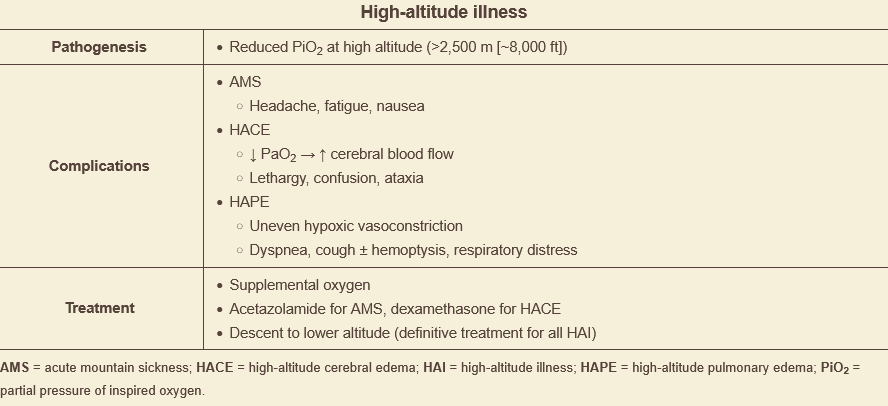

tx for high-altitude sickness?

dexamethasone